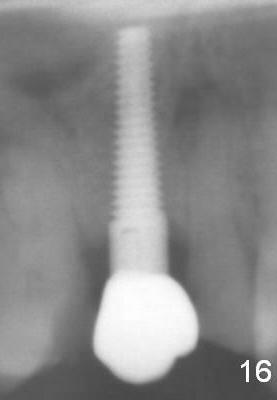

A 72-year-old man is a bruxer with #3 cusp fracture with chronic periapical radiolucency (Fig.1 *) and #4 acute crack.  It appears reasonable to take care of emergency (#4 extraction and immediate implant (Fig.3-7: 4.5x20 mm, 45 Ncm)) followed by root canal therapy or extraction for #3.  Eight (Fig.8) and 14 (Fig.9-11) days postop, the patient is doing fine and the wound heals normally.  But he does not agree any treatment for #3, since it is asymptomatic in spite of a fistula associated with the tooth (Fig.8,9 >).  Three months postop, the patient is still asymptomatic and is ready for #4 restoration since the tooth #28 cracks.  Follow-up PA shows the persistent distal gap (Fig.12 >, as compared to Fig.4), accompanied with crestal bone resorption (*).  Clinically the implant has mild mobility and light tenderness. The patient still refuses #3 treatment. It appears that the implant has failed to osteointegrate.  In brief, do not place an immediate implant next to active infection.

Five and a half months postop, the distal gap appears to have reduced (Fig.13 >).  Clinically the implant is stable and is ready for restoration.  It is advisor able to watch those asymptomatic immediate implants with minimal mobility.  It takes time to osteointegrate the immediate implant considering the peri-implant space.

Eight months post cementation, CBCT shows periapical infection of the neighboring teeth (Fig.14 *).  There is still apical bone for a longer implant (Fig.14 green line, Fig.15 *).  The implant functions 1.5 years post cementation. When the implant at the lower bicuspid fails, the patient reveals that he is a diabetic.  The latter is the main reason of delayed healing.